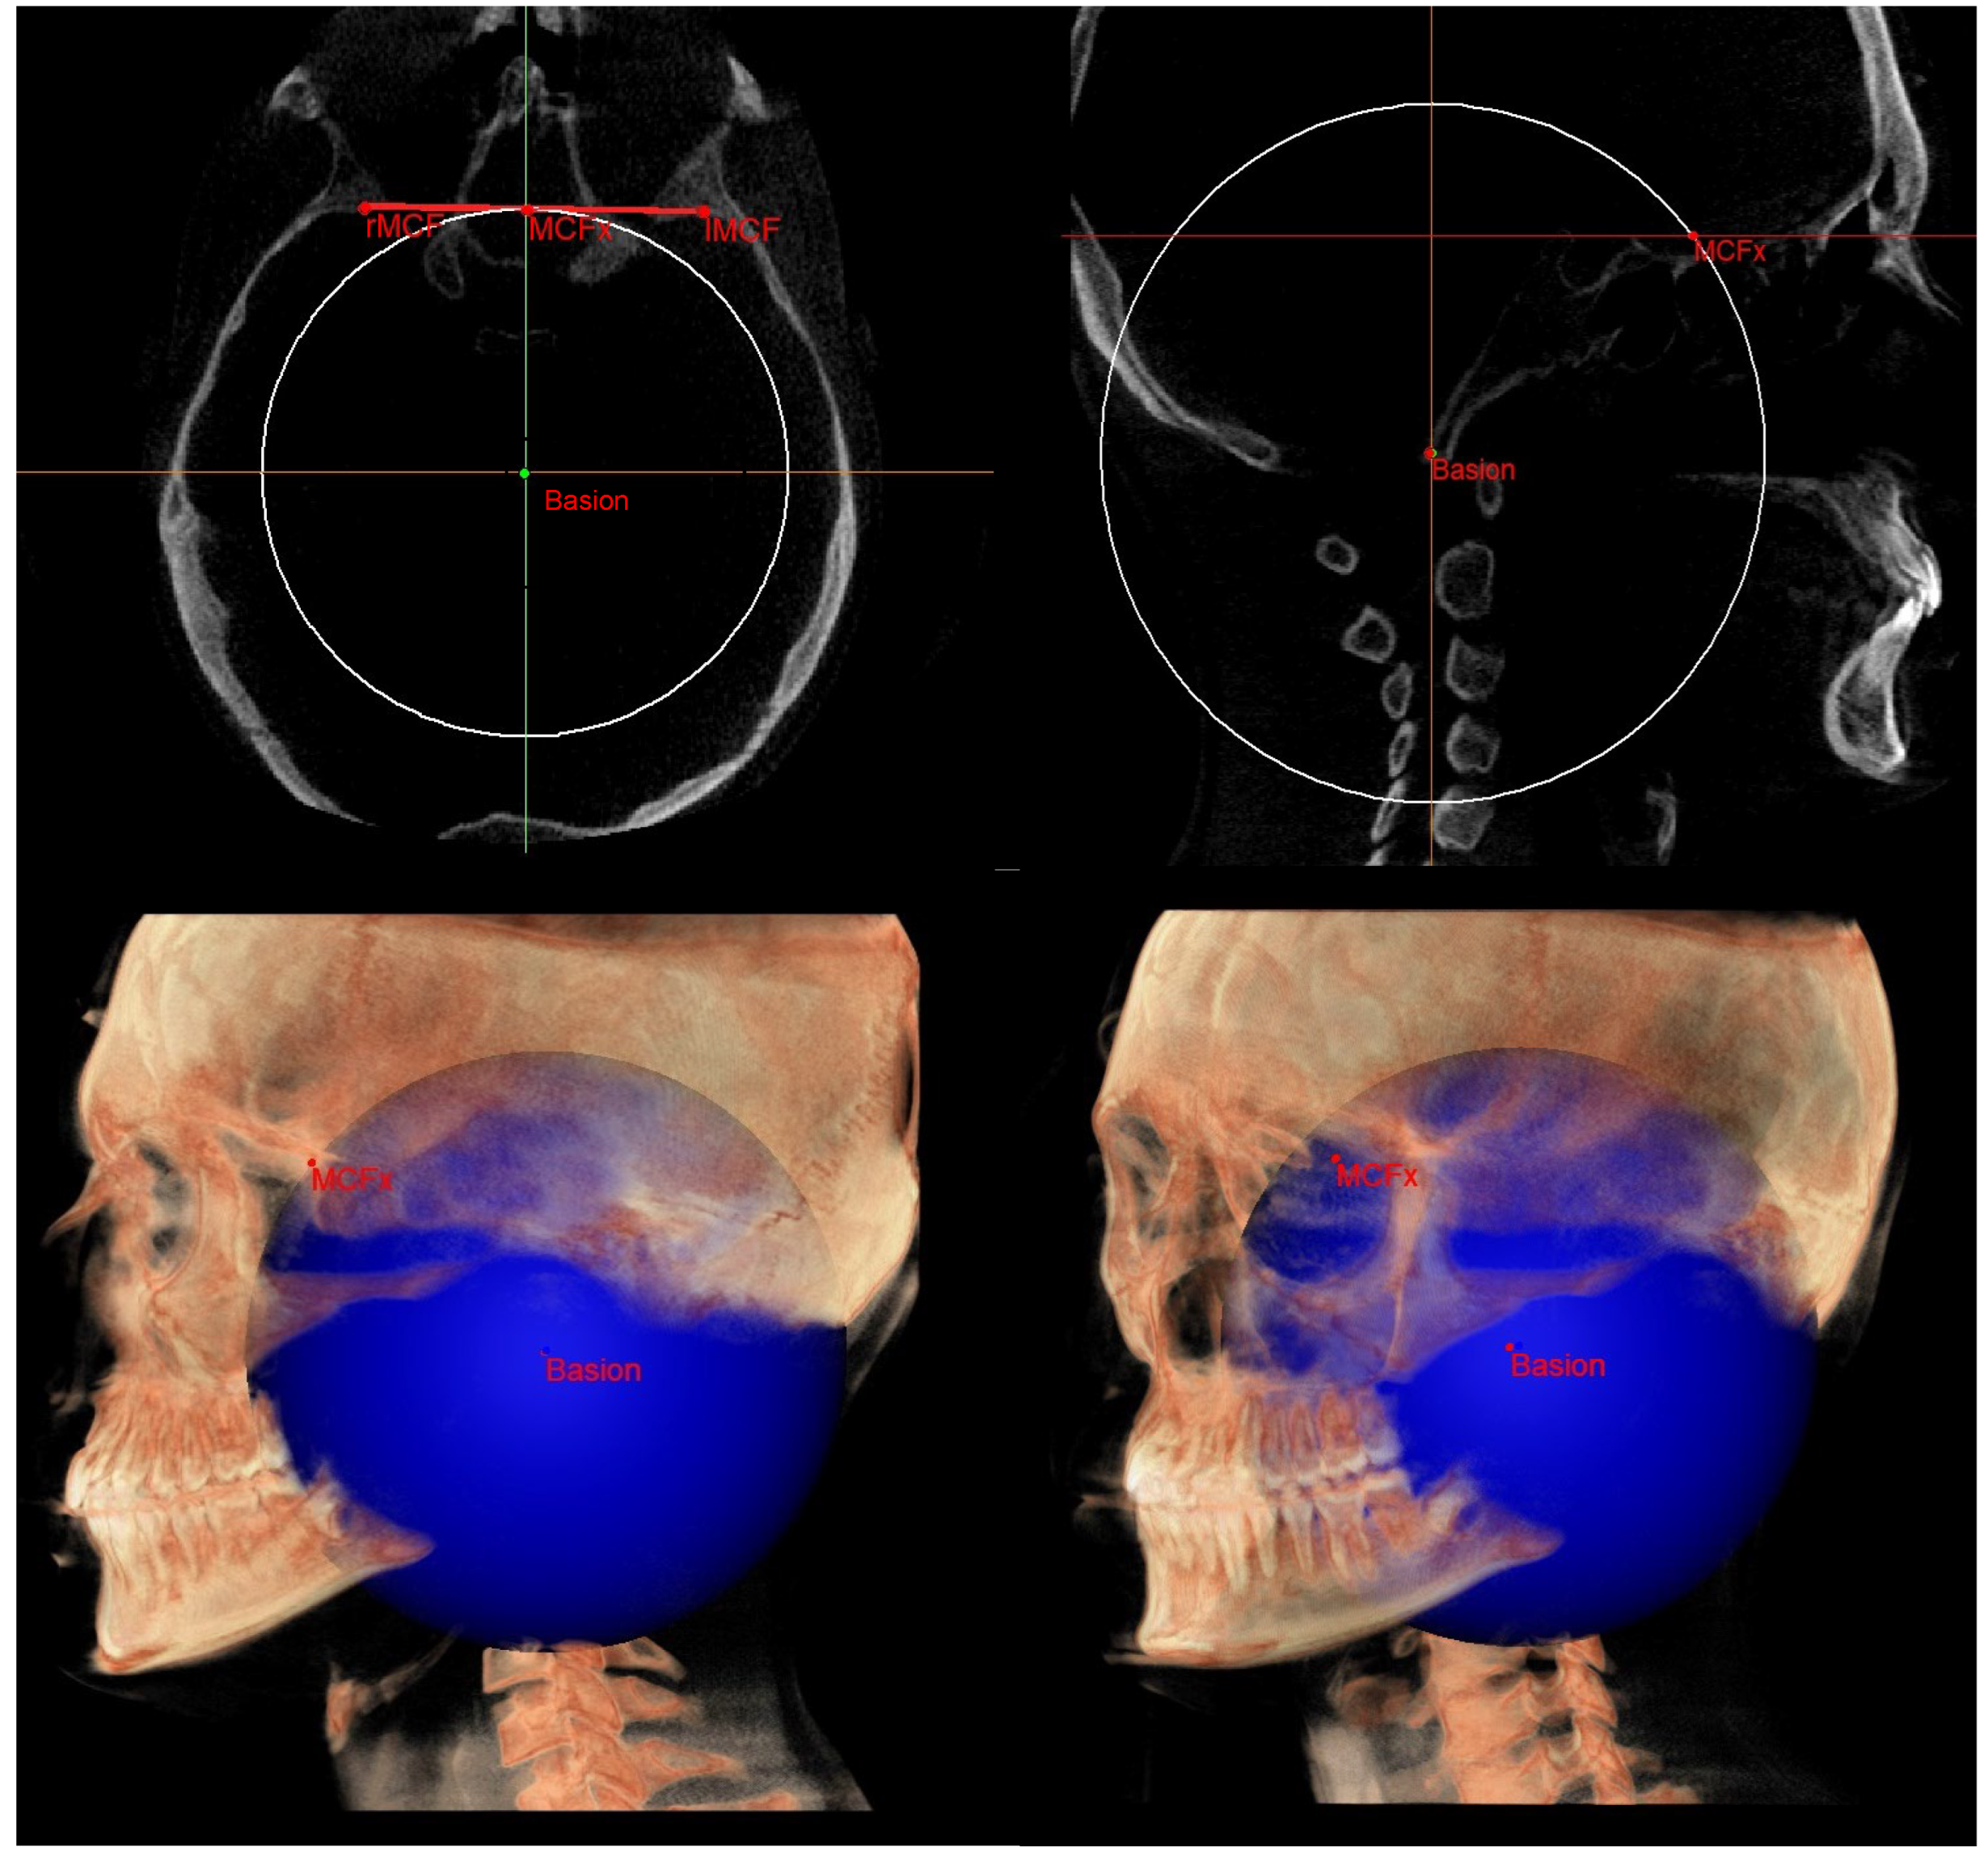

| SE neutral (SEn) | / | Point of a circumference with center in Ba and radius equal to MCFx, in which an angle of the skull base equal to 40.3° is obtained | / |

| Right SE neutral (rSEn) | / | Point taken arbitrarily on the right side of the SEn on the same arc of circumference | / |

| Left SE neutral (lSEn) | / | Point taken arbitrarily on the left side of the SEn on the same arc of circumference | / |

| Middle point MCF (MCFx) | / | Point of intersection between the plane on which the Ba lies and a line joining the left and right MCF | / |

| MCF neutral (MCFn) | Plane passing through the Ba, rSEn and lSEn which forms an angle of 40.3° with the PMn at the SEn point |